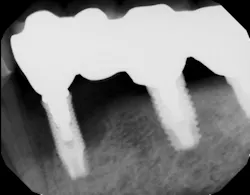

Another scenario that took place in a private practice with actual dollar amounts can be seen in treatment plan C. This patient had already paid for treatment plan B in the $5,000–$7,000 range and subsequently presented to the practice with moderate peri-implantitis. In addition to the money the patient had already invested, she would now be responsible for the financial costs of treatment plan C.

After reviewing the additional costs and lengthy healing time involved with surgery to correct the ailing implant, the overall costs associated with treatment were in the $8,000–$10,000 range, with more than three years of treatment time invested. Of important note is that most insurance companies limit the amount of reimbursement for implant-related services. When dealing with insurance companies, accurate ADA coding and claims submission are critical to facilitate services and expedite reimbursement.